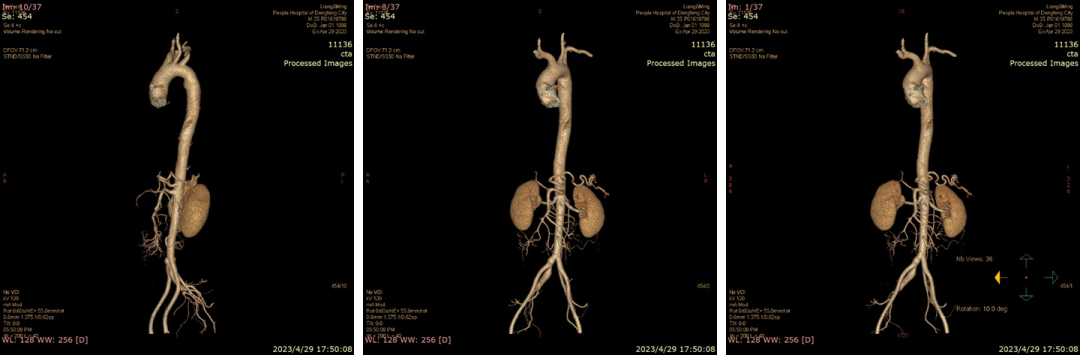

20230429CTA(当地医院初查)